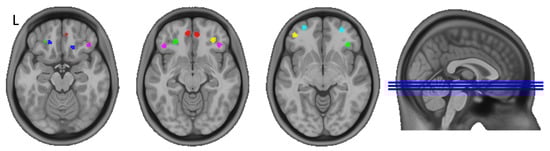

| Left Hemisphere (L) | Right Hemisphere (R) | |||||

|---|---|---|---|---|---|---|

| Seed No. | x | y | z | x | y | z |

| 1 | −7 | 49 | −12 | 6 | 47 | −13 |

| 2 | −19 | 35 | −19 | 16 | 28 | −19 |

| 3 | −26 | 36 | −13 | 37 | 32 | −8 |

| 4 | −43 | 30 | −11 | 40 | 31 | −14 |

| 5 | −42 | 46 | −8 | 31 | 39 | −12 |

| 6 | −28 | 57 | −8 | 28 | 54 | −8 |